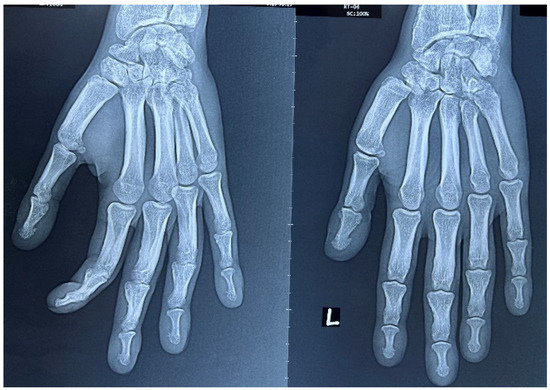

2. Case Report